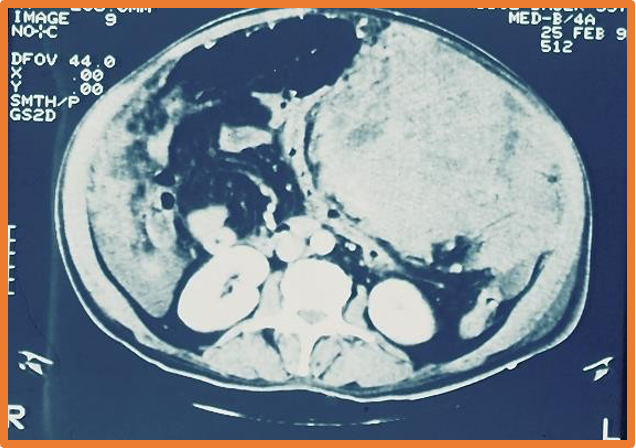

- US, CT

- U/S, CT- scalloped indentation help diagnosis.